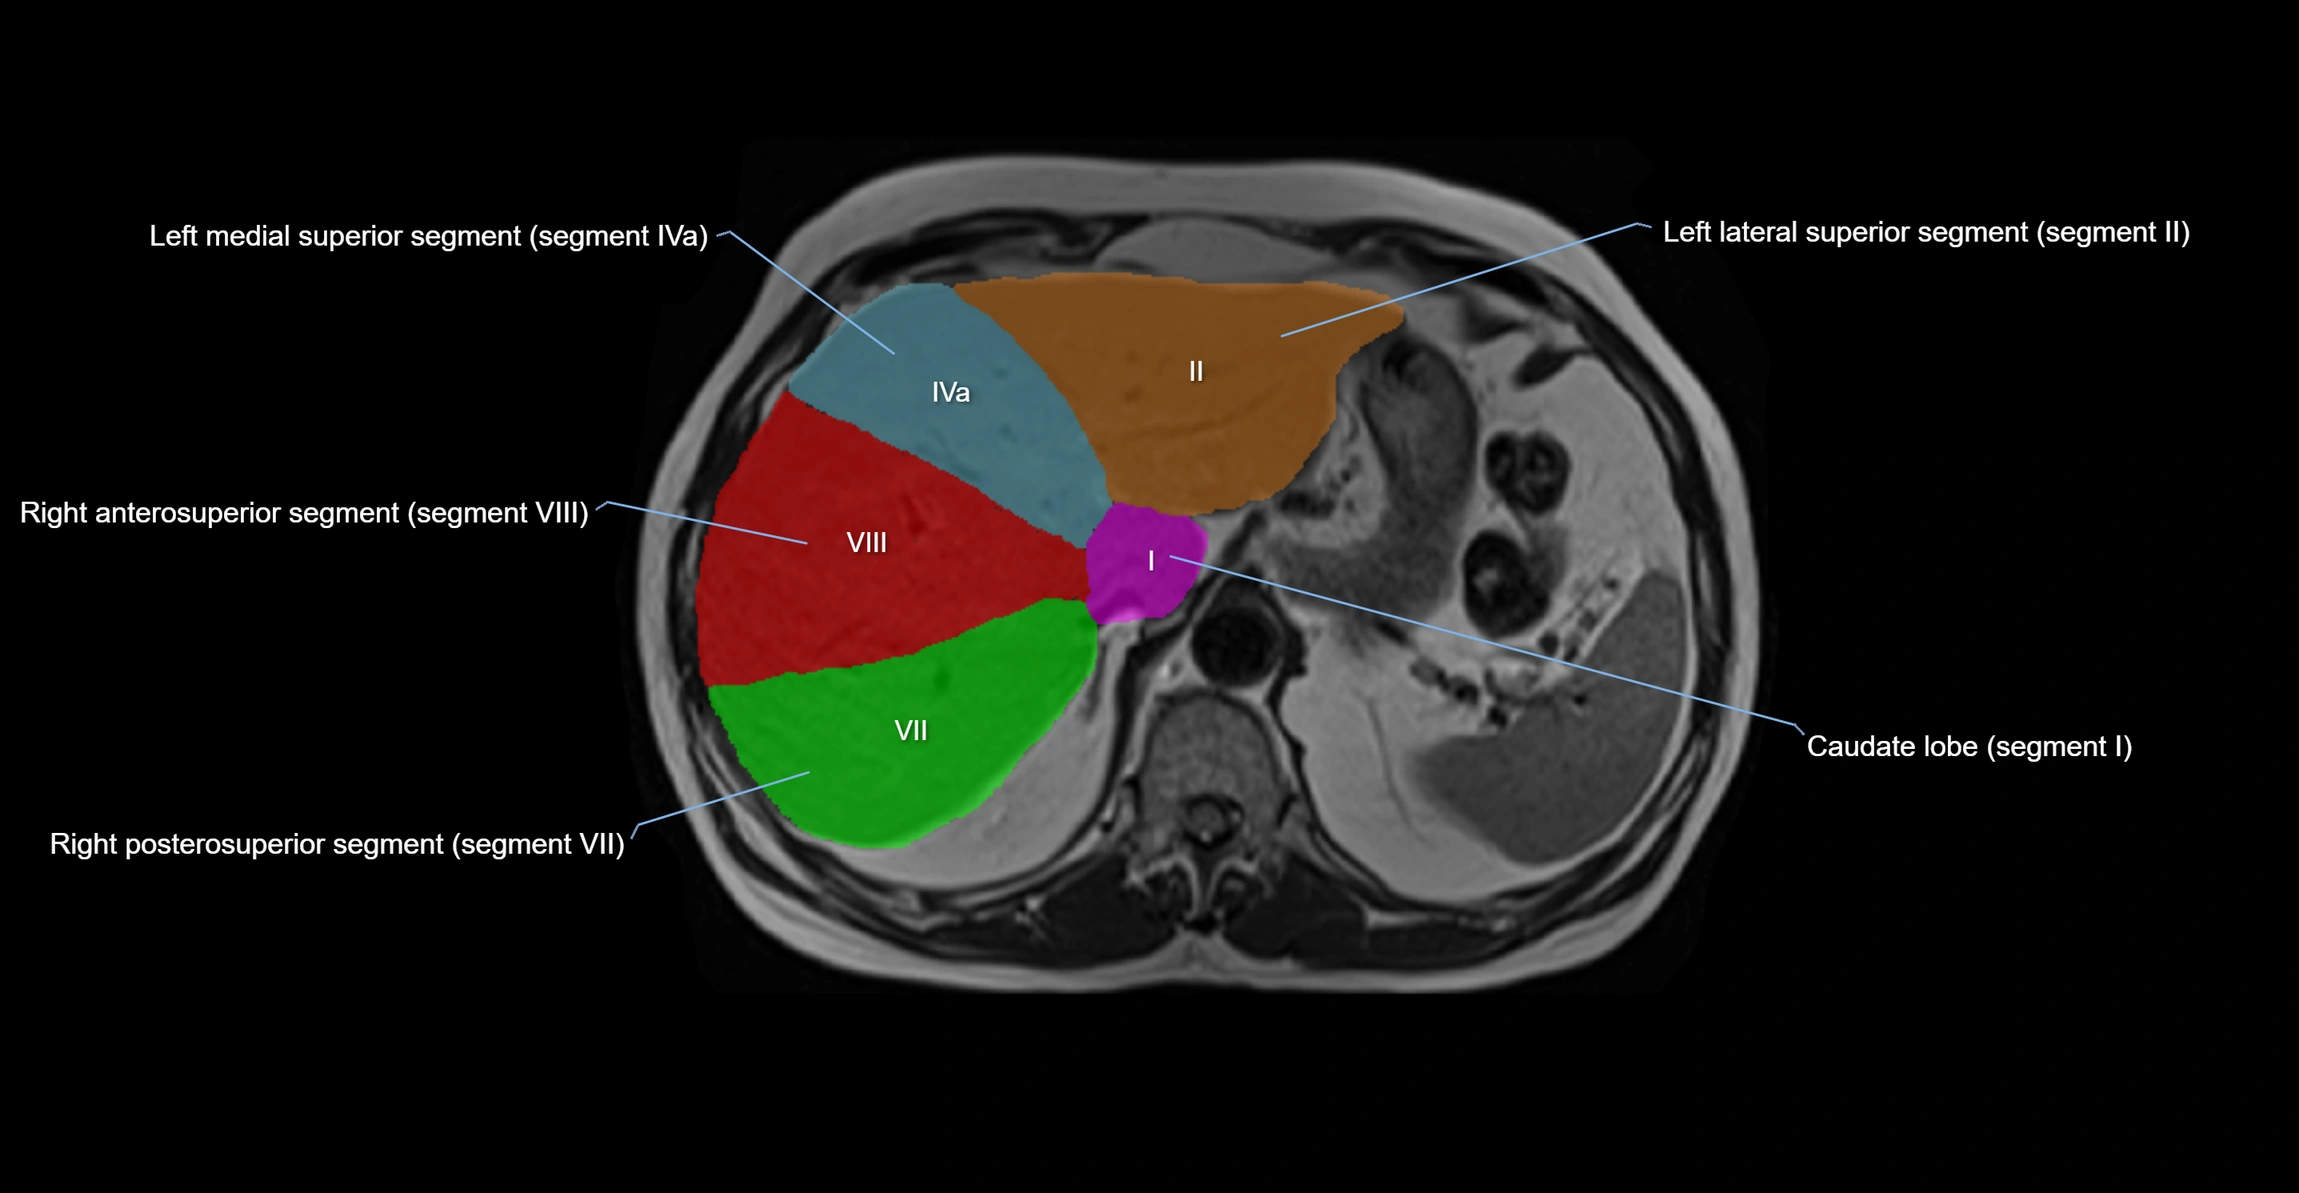

The caudate lobe of the liver is a distinct anatomical subdivision of the liver, designated as segment I in Couinaud’s classification. It lies on the posterior surface of the liver, between the fissure for the ligamentum venosum (left boundary) and the groove for the inferior vena cava (IVC) (right boundary). Superiorly, it is related to the posterior liver surface, and inferiorly it is separated from the left lobe by the porta hepatis.

The caudate lobe is unique because it receives dual portal venous and arterial inflow from both the right and left portal veins and hepatic arteries. It also has independent venous drainage directly into the IVC via multiple small hepatic veins, unlike other lobes that drain through the three main hepatic veins.

This anatomical autonomy makes the caudate lobe especially significant in liver surgery, transplantation, and hepatic venous outflow obstruction syndromes (e.g., Budd–Chiari syndrome). Enlargement of the caudate lobe is a characteristic imaging feature in chronic liver disease and cirrhosis.

MRI image

image